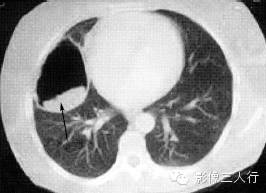

| 支气管扩张

(图1) |